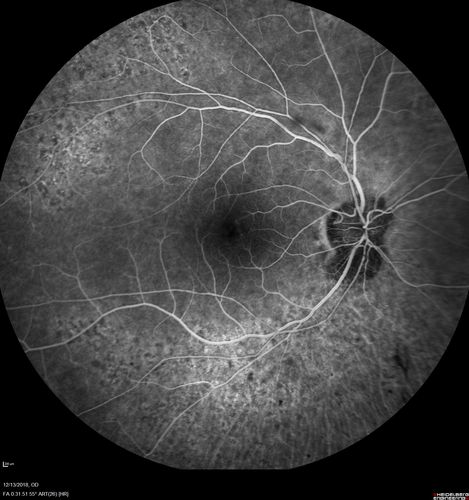

Retinitis Pigmentosa with Cystoid Macular Edema responsive to topical carbonic anhydrase inhibitors

67 year old female  She thought it was time to have her glasses changed.She has no family history of reitnal disease and has never been diagnosed with a problem.   She started having night vision trouble the last year.  Two sisters and a brother with normal vision.